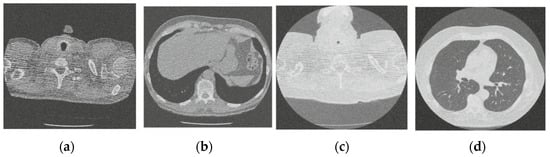

In this section, the experimental results of the proposed method over noisy CT images with their performance aspects are presented. All the experiments are performed on the standardized and simulated CT image data set with artificially introduced white Gaussian noise. Additionally, qualitative, quantitative, and graphical analysis is done to provide evidence for the efficacy of the proposed method. The reference CT image dataset is shown in Figure 2. The CT images are of [512 × 512] resolution size, which is used for consistency. This framework can work with dynamic image size, and performance commensurate to the available hardware. The image shown in Figure 2d refers to grayscale using built-in MATLAB functions before use.

Figure 2.

Online access database of original CT images [49]; (a) Reference CT1 image; (b) Reference CT2 image; (c) Reference CT3 image; (d) Reference CT4 image.